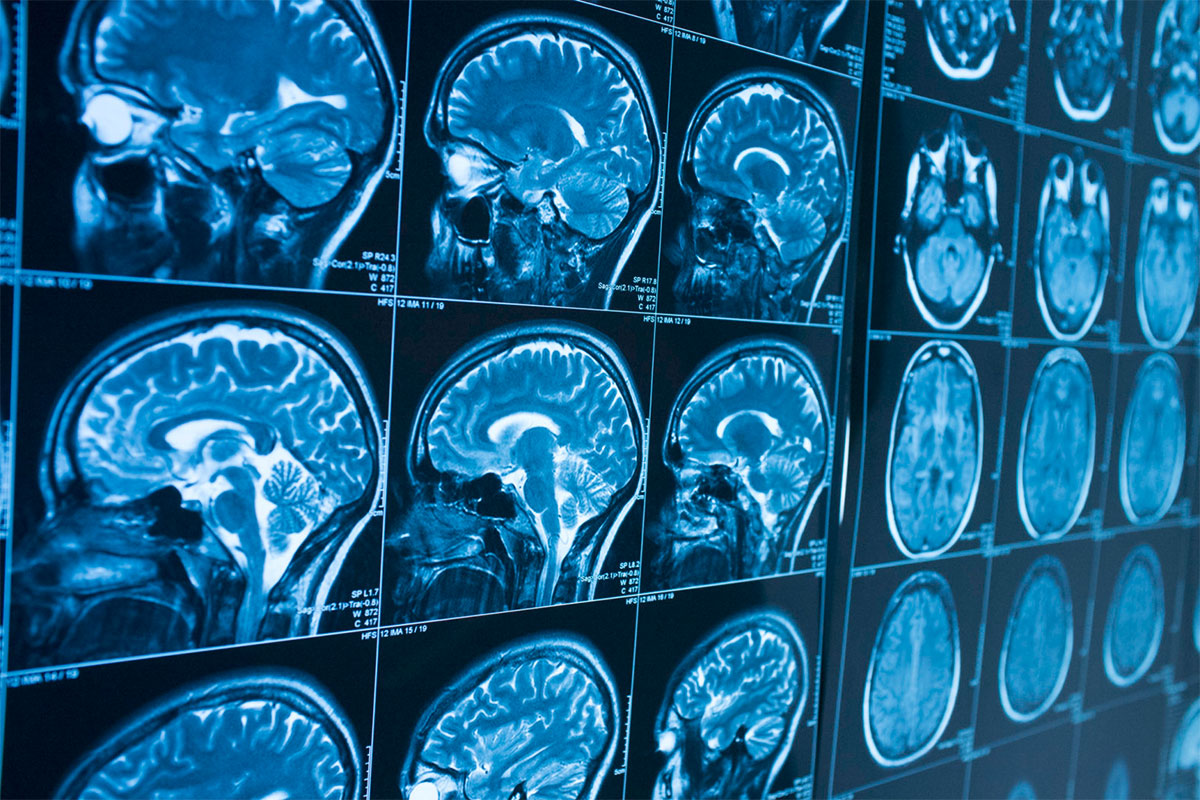

Rengeteg kutatás foglalkozik azzal, hogyan lehetne az Alzheimert a kezdeti fázisban, vagy akár még előbb is kimutatni: a módszerek között van például vérvizsgálat és olyan kütyü alkalmazása is, ami a mozgásunk megváltozását figyeli. A Bari Egyetem kutatói most egy új eljáráson dolgoznak, amely a remények szerint akár 10 évvel az első tünetek megjelenése előtt figyelmeztethet a betegség kialakulására. A kutatók a mesterséges intelligenciában bíznak; fejlesztettek egy olyan szoftvert, amely MRI-felvételek elemzése alapján állítja fel a diagnózist. A program 63 paciens adatai alapján kezdte el megtanulni, hogy milyen apró strukturális elváltozások figyelhetők meg a betegek agyában. A tanulási folyamat végeztével a szoftvernek 148, addig nem látott felvételt mutattak meg. Közöttük volt 48 olyan, amely beteg emberek agyáról készült, és 48 olyan is, amely mára beteggé vált emberek agyáról korábban, a betegség diagnosztizálása előtt készült. A program kiváló eredményt ért el: 86 százalékban helyes volt a diagnózis a betegeknél, 84 százalékban pedig a csak később beteggé váló embereknél is tudta azonosítani az Alzheimert.